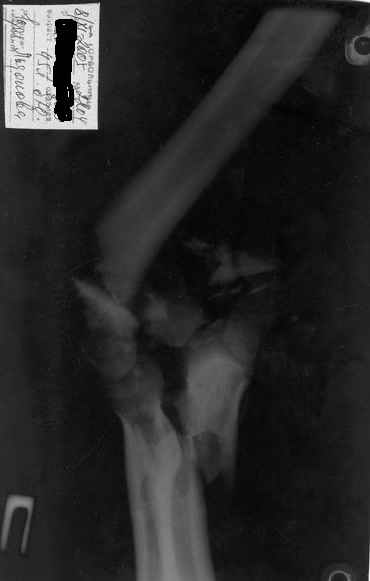

Здравствуйте, коллеги.Мужчина, 45 лет, ДТП 24.10.05. На сегодня неврологических расстройств правой кисти нет, отека нет, движения в правом плечевом и в правой кисти в полном объеме. Правый локтевой сустав сгибани 110*, разгибание 140*, наружняя ротация предплечья 45*, внутренняя 45*. Укорочение правого плеча 4 см. Больной просит у меня совет, стоит ли ему стремиться к эдопротезированию локтевого сустава.Я, к сожелению, не видел ни одного больного после эндопротезирования локтевого сустава.-- С уважением,Анатолий Борзунов

Имея небольшой опыт эндопротезирования локтевого сустава (3 операции - 2 эндопротеза типа Сиваша, и 1 - RM), считаю, что основным показанием к эндопротезированию этого капризного сустава является его гипермобильность (в результате перелома с формрованием разболтанного ложного сустава см. форум от 06.04 2006), или выраженный болевой синдром в сочетании с тугоподвижностью (что встречается у наших больных с гемофилической артропатией). Собственные результаты в целом неплохие - отсутствие болей и гипермобильности, однако, имеется некоторое ограничение разгибания. Сама

операция сопровождается мобилизацией локтевого нерва, а в условиях нарушенной анатомии сросшегося оскольчатого перелома имеется высокая вероятность его травматизации во время выделения, с вытекающими проблемами.

Для данного пациента может потребоваться изготовление индивидуального протеза с длинной ножкой.